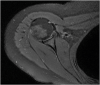

The rotator cuff is a group of four muscles and tendons surrounding the shoulder joint providing it strength and stability. The rotator cuff consists of the subscapularis, supraspinatus, infraspinatus and teres minor. Many shoulder complaints are caused by rotator cuff pathology such as impingement syndrome, tendon tears and other diseases e.g. calcific tendonitis. Diagnosis starts with clinical history and physical examination, after which imaging is often used to help confirm clinical findings depending on the differential diagnosis. The aim of the article is to review the frequently used imaging modalities to assess the rotator cuff and cuff-related disease, specifically focusing on radiography, ultrasonography and magnetic resonance imaging. This article will outline the advantages and disadvantages for each modality and illustrate typical radiological findings of common rotator cuff pathologies.